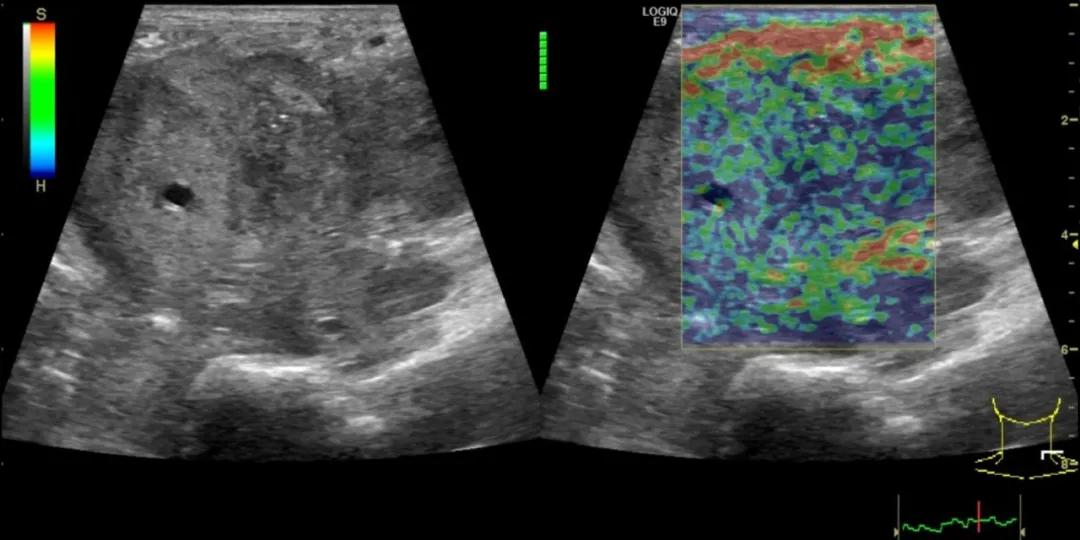

第四例是胸腺癌化妆包,术后、化疗之后淋巴结转移,肿块范围巨大,99mm*61mm,边界不清,呈浸润状,肿块包绕颈动脉,颈内静脉压闭,症状明显。由于患者放化疗也不敏感、血供非常丰富,于是采取多点姑息性消融。姑息性消融后未实现完全消融,病灶大片坏死,肿胀疼痛得到明显的缓解,后续患者未再来复查。

(病例4图例)